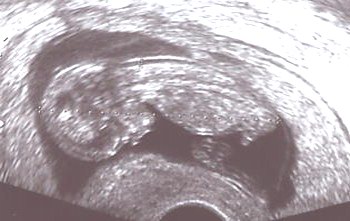

Am Ende des ersten Schwangerschaftsdrittels findet man häufig eine Wasseransammlung (Nackentransparenz) unter der Haut des kindlichen Nackens. Ist diese Schicht größer als normal, kann dies auf chromosomale Anomalien oder andere Erkrankungen des Kindes hinweisen (z. B. Herzfehler).

Durch die Messung der kindlichen Nackentransparenz (NT-Messung) kann von der 12. bis 14. Schwangerschaftswoche durch zertifizierte Ärzte eine individuelle Risikoberechnung in Bezug auf die Trisomie 21 durchgeführt werden.

Die Messung erfolgt durch eine vaginale oder abdominale Ultraschall-Untersuchung.

| unauffällige Nackentransparenz | exakte Darstellung im hochauflösenden Ultraschall | auffällige NT, weitere Diagnostik erforderlich! |

Diese Untersuchungen bieten keine Diagnose, sondern eine individuelle Risikoabschätzung. Ein auffälliges Testergebnis bedeutet nicht, dass das Kind eine Chromosomenanomalie oder einen Herzfehler hat, sondern es zeigt an, ob ein höheres Risiko besteht. Dann sollte ggfs. eine weiterführende Diagnostik erfolgen. Umgekehrt kann das Risiko bei entsprechender NT-Messung sich auch vermindern. Ein sicherer Ausschluss von Chromosomenstörungen ist letztlich nur durch eine Fruchtwasserpunktion oder Chorionzottenbiopsie möglich.